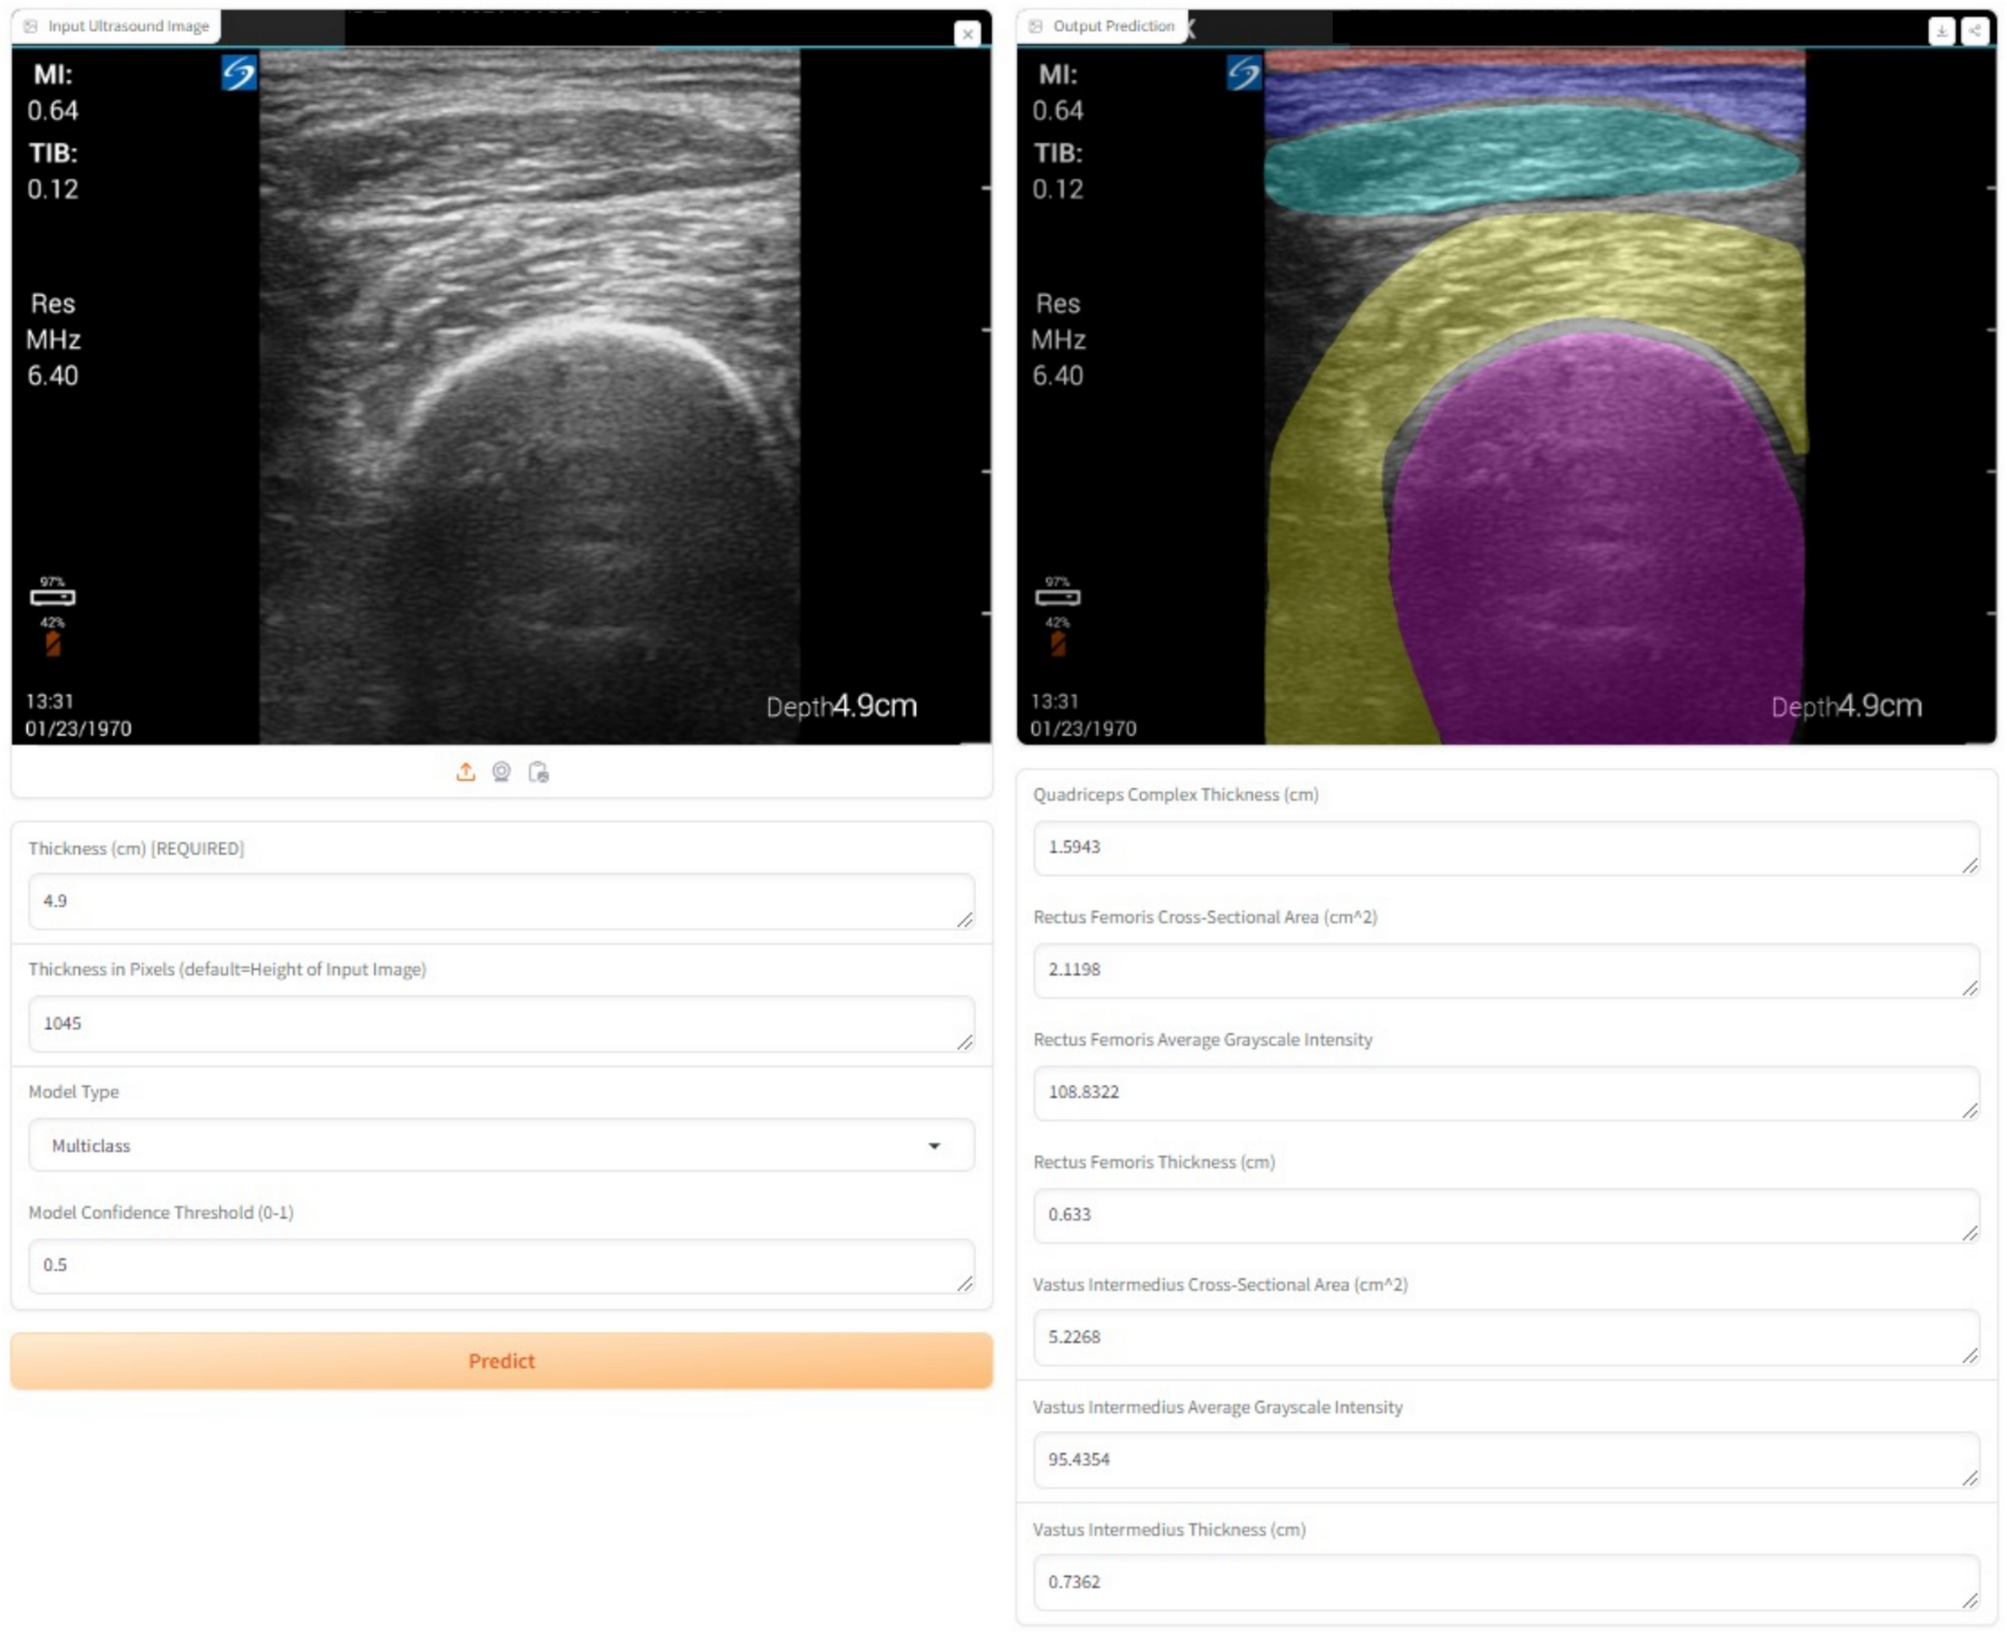

Fig. 3

MyoVision-US graphical user interface hosted on HuggingFace, a commonly used platform for building, training, and deploying machine learning models, with results of multiclass analysis and measurements shown. Skin (red), adipose tissue (blue), rectus femoris (yellow), vastus intermedius (aqua), and femur (pink) are segmented and shown.